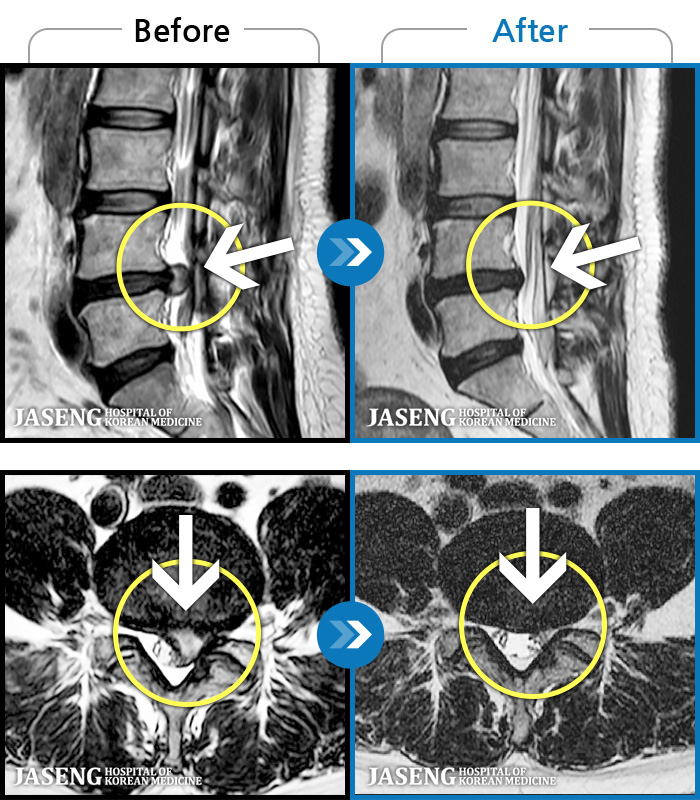

• 허리디스크